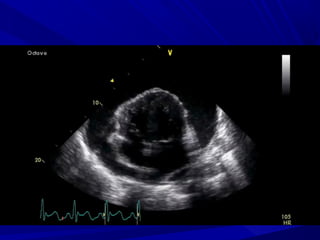

ECHO-CARDIOGRAPHYECHO-CARDIOGRAPHY

Thick pericardium/calcifiedThick pericardium/calcified

““Small ventricles”Small ventricles”

““Big atria”Big atria”

IVC distension, hepatic veins distensionIVC distension, hepatic veins distension